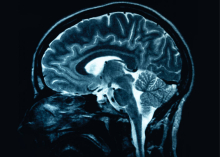

A new discovery by McGill researchers sheds light on how we retain memories over time, even though brain activity is constantly changing.

Published in Nature, the preclinical study found the brain’s internal compass remains remarkably stable over time. The findings suggest this steady sense of direction may act as an anchor for memory.

How stepping into nature affects the brain

Spending time in nature, even briefly, triggers changes in the brain that calm stress, restore attention and quiet mental clutter, a new study has found.

Researchers at McGill University and colleagues at Adolfo Ibáñez University in Chile have examined more than 100 brain-imaging studies from various disciplines. The result is one of the most comprehensive reviews to date of how the brain responds to nature.